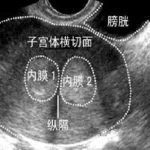

子宫纵隔是导致流产,不孕,宫外孕常见原因,是先天发育畸形!北京安太医院纵隔分离后放置梨形支架可以正常怀孕分娩!